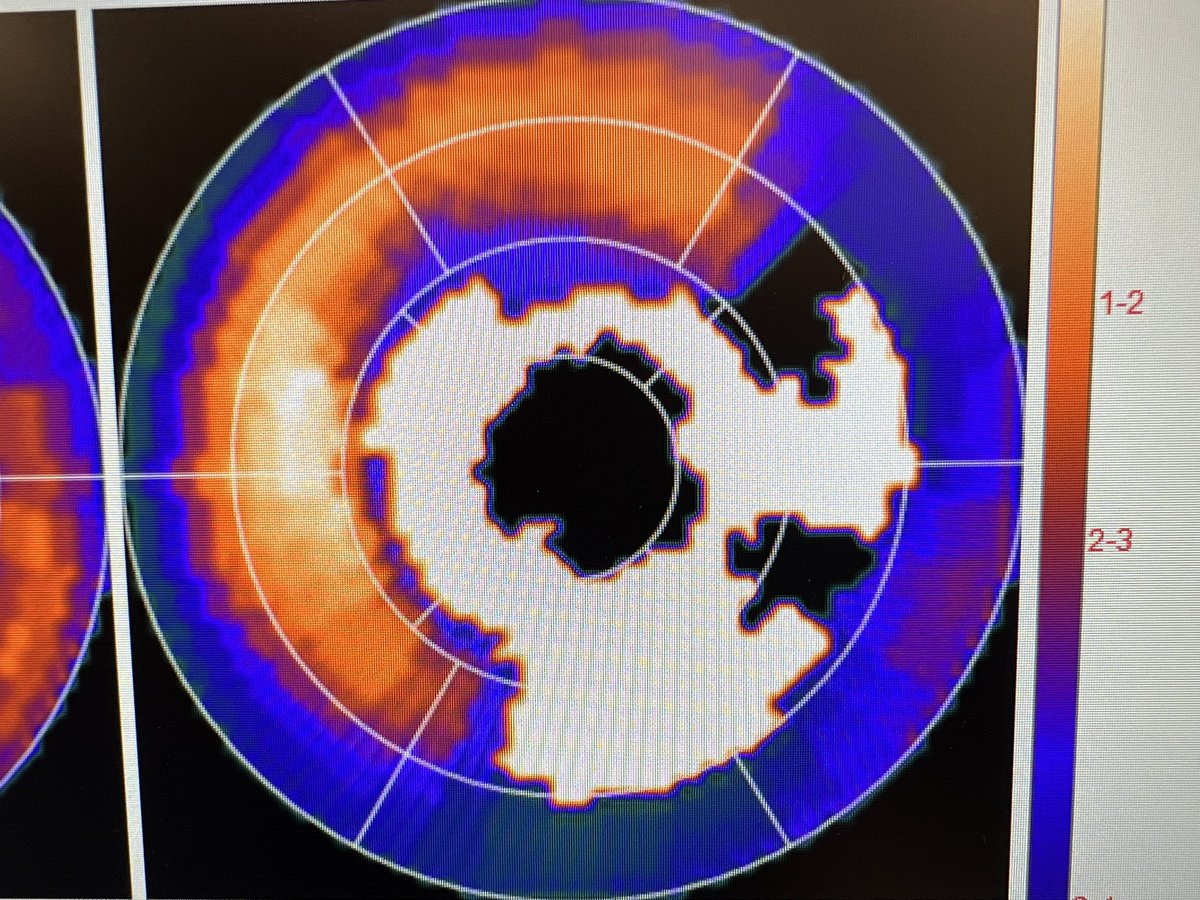

@ATheartdoc

I think…the patient…has ischemia!